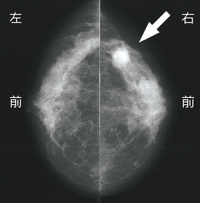

【図2】マンモグラフィ 頭尾方向撮影

乳がんの診断として重要な検査は、「視触診」に加え、「マンモグラフィ」「乳房超音波検査」などの画像診断と、生体から採取(生検)した細胞や組織を直接観察する「細胞組織学的検査」です。 |

乳がんの早期発見には「マンモグラフィ」、「超音波」などの画像診断による乳がん検診を受けることが不可欠です。視触診だけの検診は意味がありません。平成17年からは、厚生労働省の指導により各地方自治体による、視触診とマンモグラフィを組み合わせた検診が始まっています。マンモグラフィは、40歳代の女性には縦・横の2方向撮影を、50歳以上の女性には縦方向の1方向撮影を行うことになっており、隔年での検診が行われています。また、平成21年度からは一定の年齢の方にはクーポン券による無料検診が行われていますので、ぜひ検診に出かけてください。 |